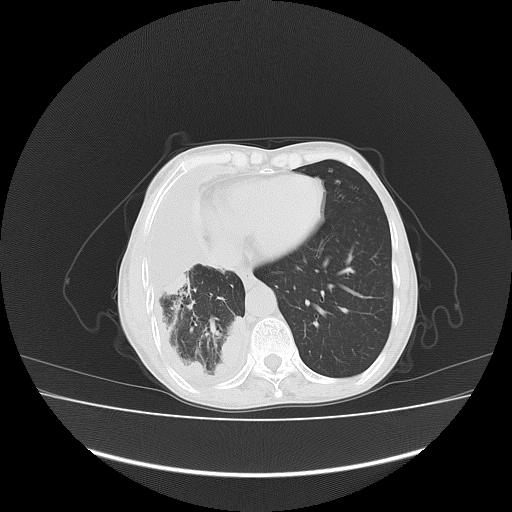

可见多发肺内病灶,且胸膜病灶较多有圆球状而非丘状,多考虑胸膜转移瘤伴胸腔积液,右侧胸廓缩小固定,且部分病灶呈丘状,尚不除外恶性胸膜间皮瘤伴肺内转移

恶性胸膜间皮瘤伴肺内转移可能性大;或胸膜、肺内均为转移瘤,左肺下叶亦见多发小结节影。

右侧胸廓塌陷,右侧胸膜广泛增厚并见多发胸膜结节,右侧少量胸腔积液并包裹。

右侧胸膜转移瘤,原发灶可能就在在右肺,另外建议检查右侧乳腺.

胸膜转移瘤  包裹性胸腔积液  肺内转移

右胸腔结节均考虑来自胸膜(部分来源于叶裂),考虑胸膜间皮瘤或转移瘤.